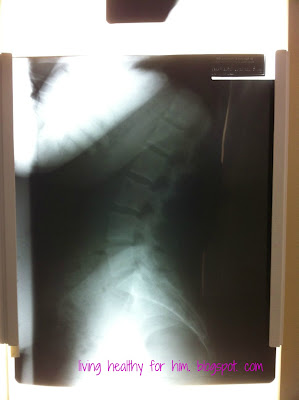

Bad News #3- When he first looked at this picture, he asked me “Have you ever been diagnosed with scoliosis?” No. “Well, you certainly have some going on here.” As you can see, my spine doesn’t exactly resemble a straight spine. It is all sorts of wonky. So you can see why my back has been hurting.

Now get this. This was the most exciting news Dr. Pochucha gave me! My hips are not lined up at all. My pelvic bone is titled and my lumbar vertebrae are squishing nerves affecting several different organs in my body. That certainly doesn’t sound like exciting news. But it is.

I finally have answers to why I had a c-section. He asked if I had irregular and heavy periods. YES. And then I told him about my delivery. He asked if I had an epidural. YES, I HAD 3 FAILED EPIDURALS. Turns out that my lumbar vertebrate were/are smooshing my nerve that relays messages to the uterus which explains my crazy irregular, heavy, painful periods and explains my difficult delivery. This explains why my contractions were never strong enough to progress my delivery past a 4. And once I had an epidural, that just shut the whole works down. Once I had the epidural, there was absolutely no way that I would deliver vaginally. The impulse was already being weakened by the smooshing of the nerve prior to the epidural and the epidural just turned off any chance of the nerves telling the uterus to contract. It didn’t matter how much pitocin they gave me and they gave me ALOT of pitocin! I was doomed from the moment they gave me the epidural.